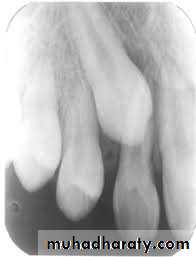

The radiographic views that can be used include;periapical, occlusal, OPG, lateral skull view cone beam CT (CBCT) can also be used. The

periapical radiograph provides a detailed view of the tooth, surrounding bone, root formation, the presence of root resorption of the adjacent lateral incisor or the presence of any pathology. Localization of the canine is important especially when it can not be determined clinically. Methods of localization include:

• Buccal object rule (parallax method, tube shift technique) in which two periapical films are taken, shifting the tube horizontally distally between exposures, if the un-erupted tooth moves in the same direction in which the tube is shifted it is localized palatally, if it moves in opposite direction it is buccally located, in a rule called SLOB (Same Lingual Opposite Buccal).

• In shifting the tube vertically inferiorly between exposures; the buccally located tooth will move inferiorly while the palatally impacted tooth will move superiorly.

• Vertex occlusal projection; which produces an axial view of the incisors, will demonstrate the bucco-palatal localization of the canine.

• Periapical occlusal method; uses a standard periapical view and an occlusal view to give two different views of the impacted tooth.

• OPG; can be used to localize impacted canine on the basis that palatally impacted canine appear magnified. It can also demonstrate the vertical angulation and its height.